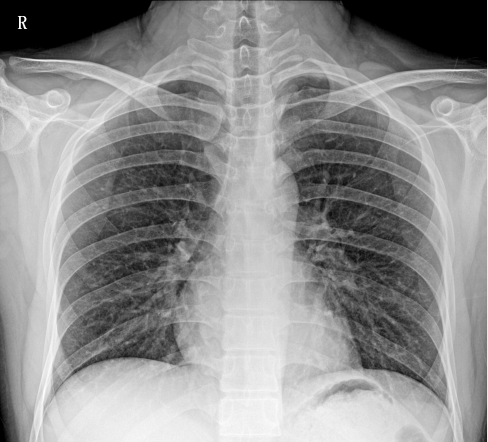

移動(dòng)DR相比只能固定作業(yè)的固定DR相比,移動(dòng)DR因其便攜性、可移動(dòng)性、操作靈活、擺位方便、占地面積小等優(yōu)勢(shì),成為ICU、發(fā)熱門診、防疫病區(qū)最為緊急采購(gòu)的需求設(shè)備。在此次新冠治療中,肺炎影像學(xué)診斷是新型冠狀病毒感染的重要判斷標(biāo)準(zhǔn)之一,CT、DR等醫(yī)學(xué)影像檢測(cè)設(shè)備發(fā)揮了重要作用。因此,移動(dòng)DR被列入國(guó)家《重大疫情救治基地應(yīng)急救治物資儲(chǔ)備清單》。下面就大家介紹一下普愛PLX5100型移動(dòng)DR的產(chǎn)品性能和工作站功能。